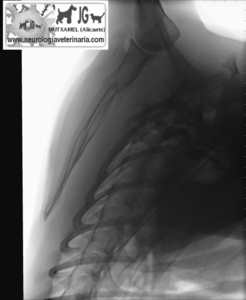

Radiografía del mismo paciente en el momento del accidente (nótese el neumotórax consecuente a la fractura de escápula) |

Nótese la perforación de la caja torácica |